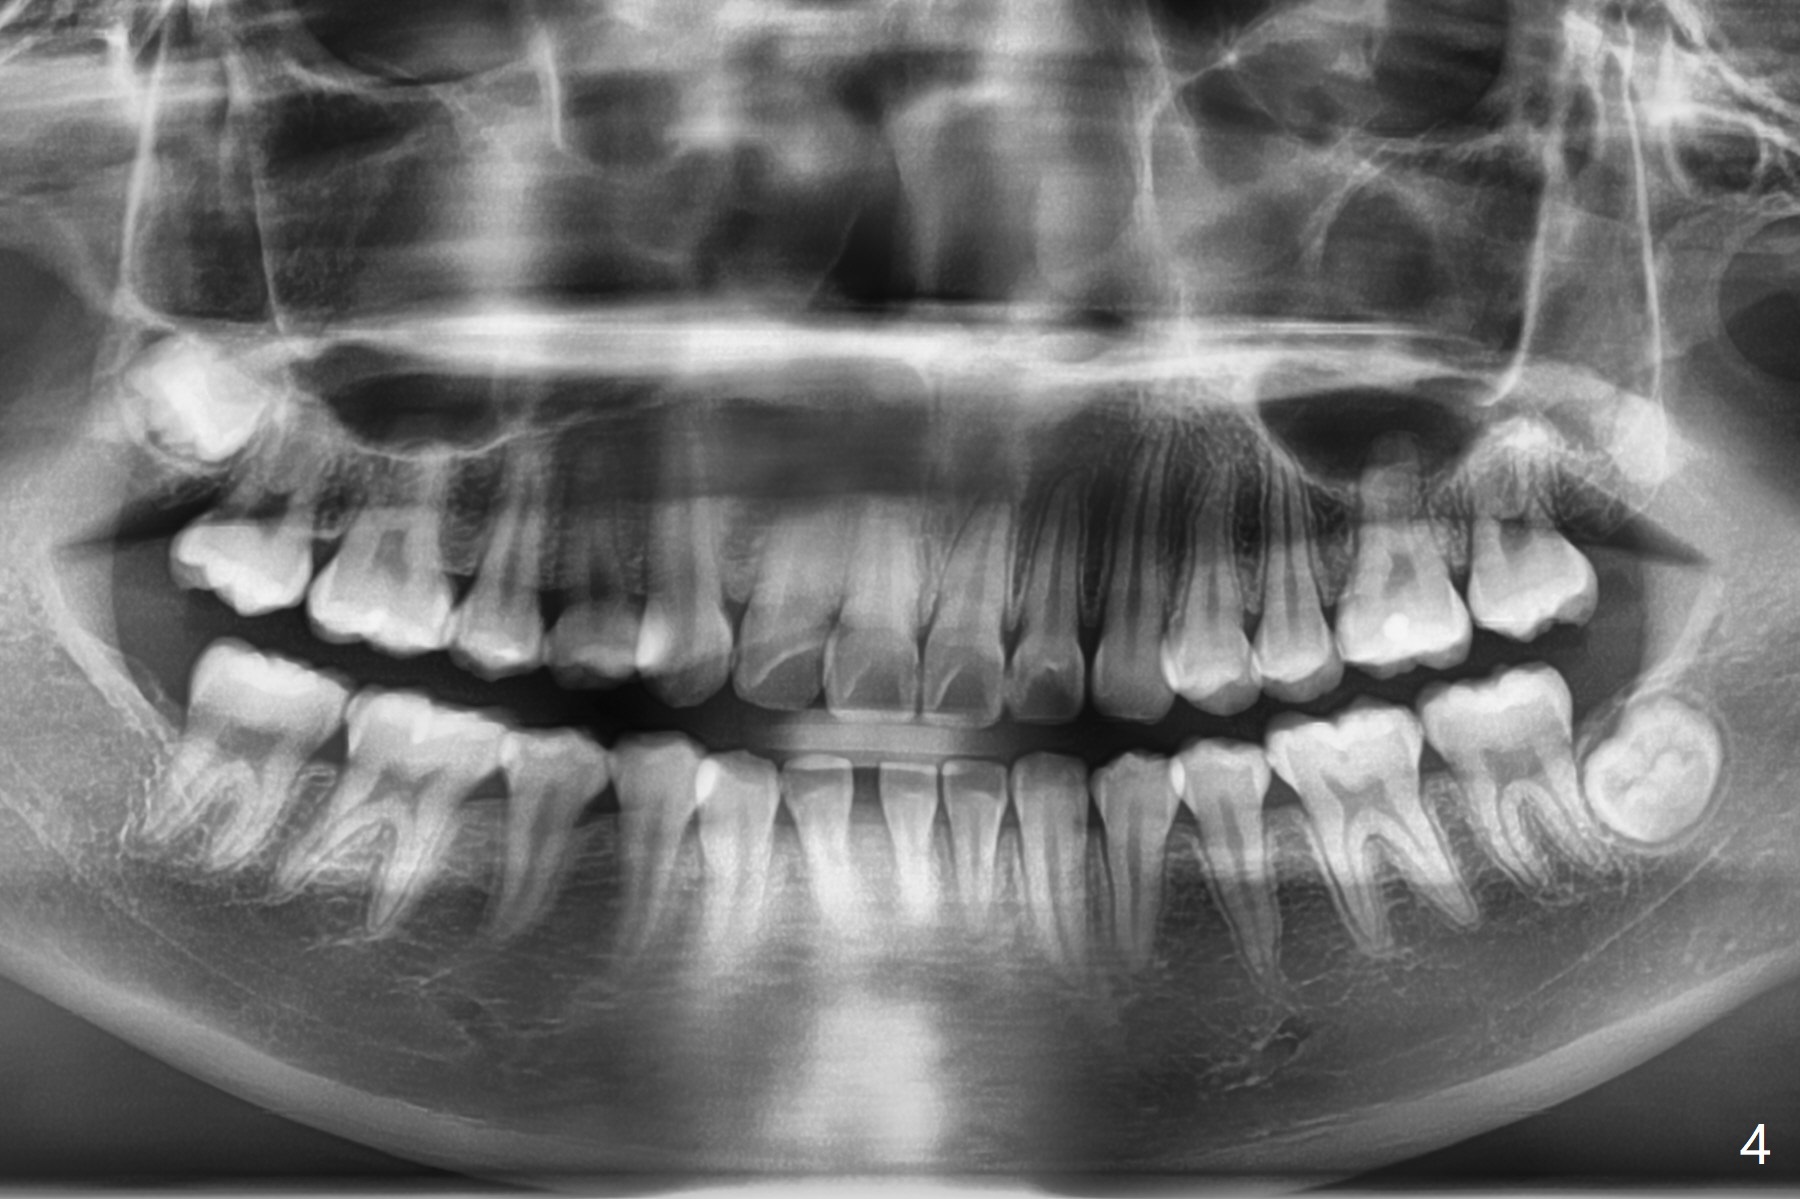

13岁女孩面型正常,先天性缺失右下1(图一,四,七),前牙深覆盖(图二),邻牙扭转(图三),治疗计划使用隐形矫正器,上牙片切,内收,关闭下切牙间隙(图八)。片切前发现上切牙邻面龋(图五,六),最大一个已经修补(右上2),不知其余小的龋坏能否片切,涂氟保守处理?不过她有龋坏易感性,以前乳牙龋坏。邻面片切后,上,下颌分别用无色和蓝色树脂做attachments(图九)。不明白的是Reciprocating saw远不如wheel利索。